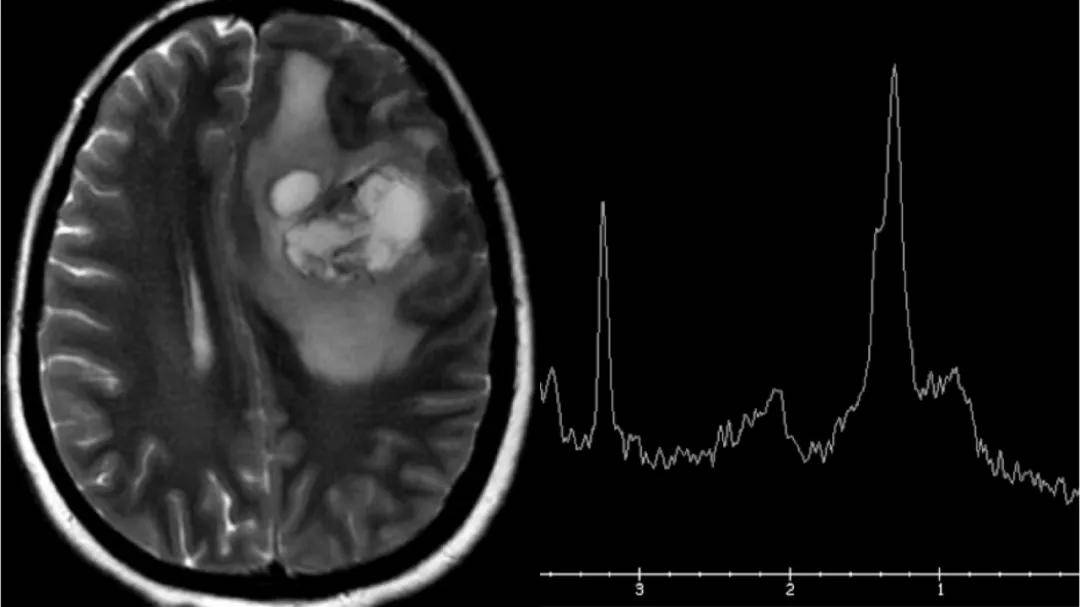

脑功能成像

(DTI)

核磁波谱成像